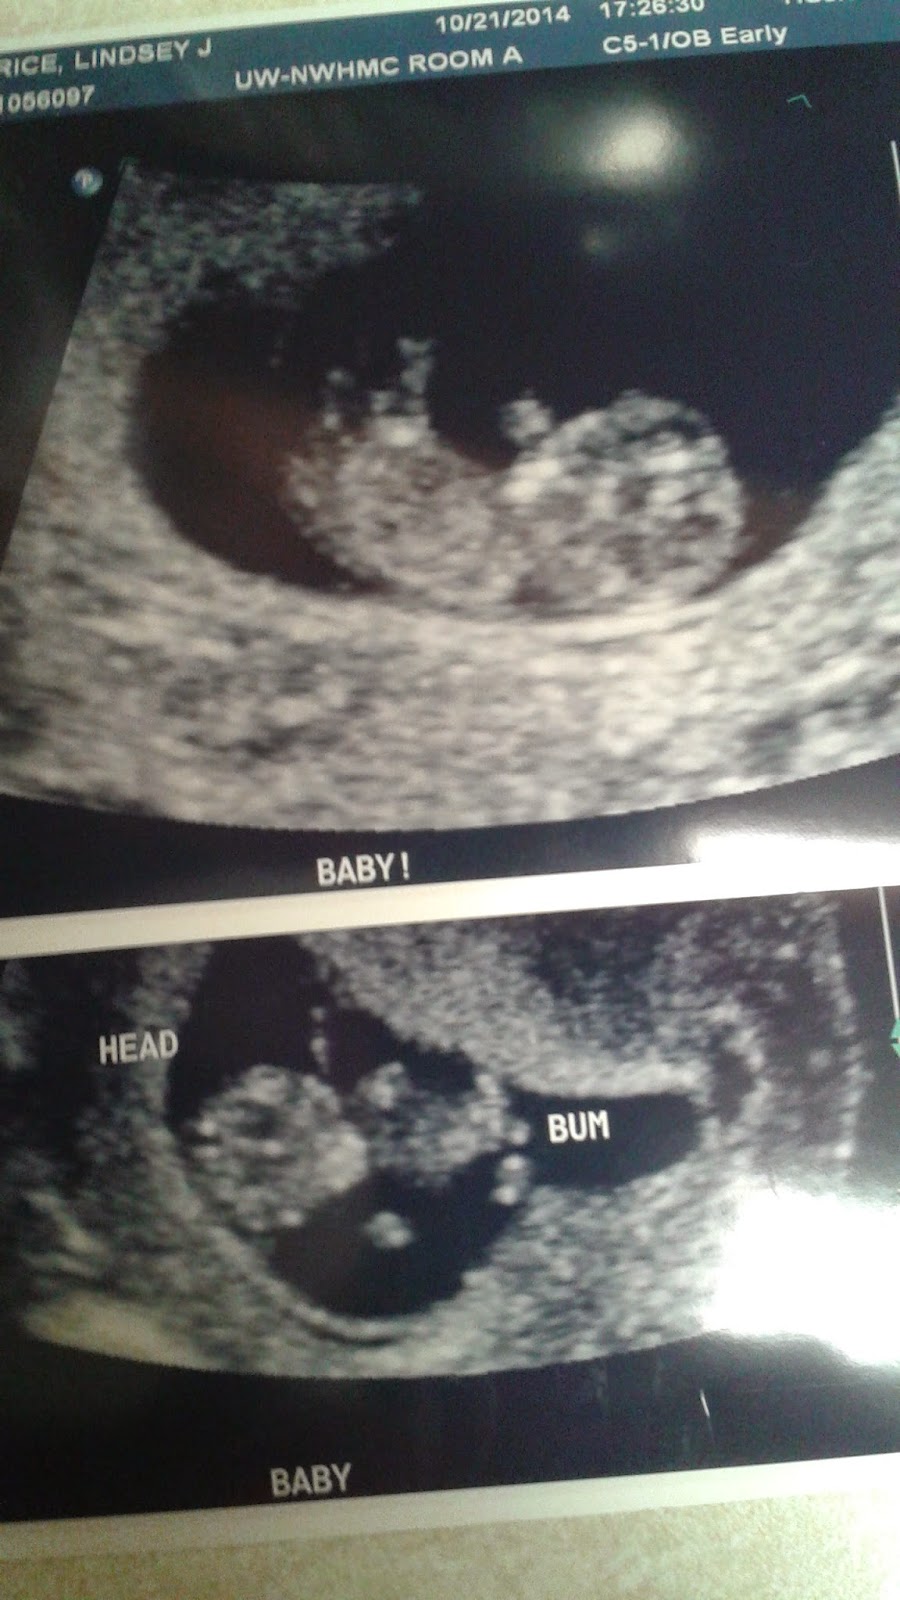

My body has been quite off since Logan was born so I really had no idea how far along I was. A few weeks after the test, mom came with me to a dating ultrasound where we were surprised to see little arms and legs moving around already.

10 weeks!